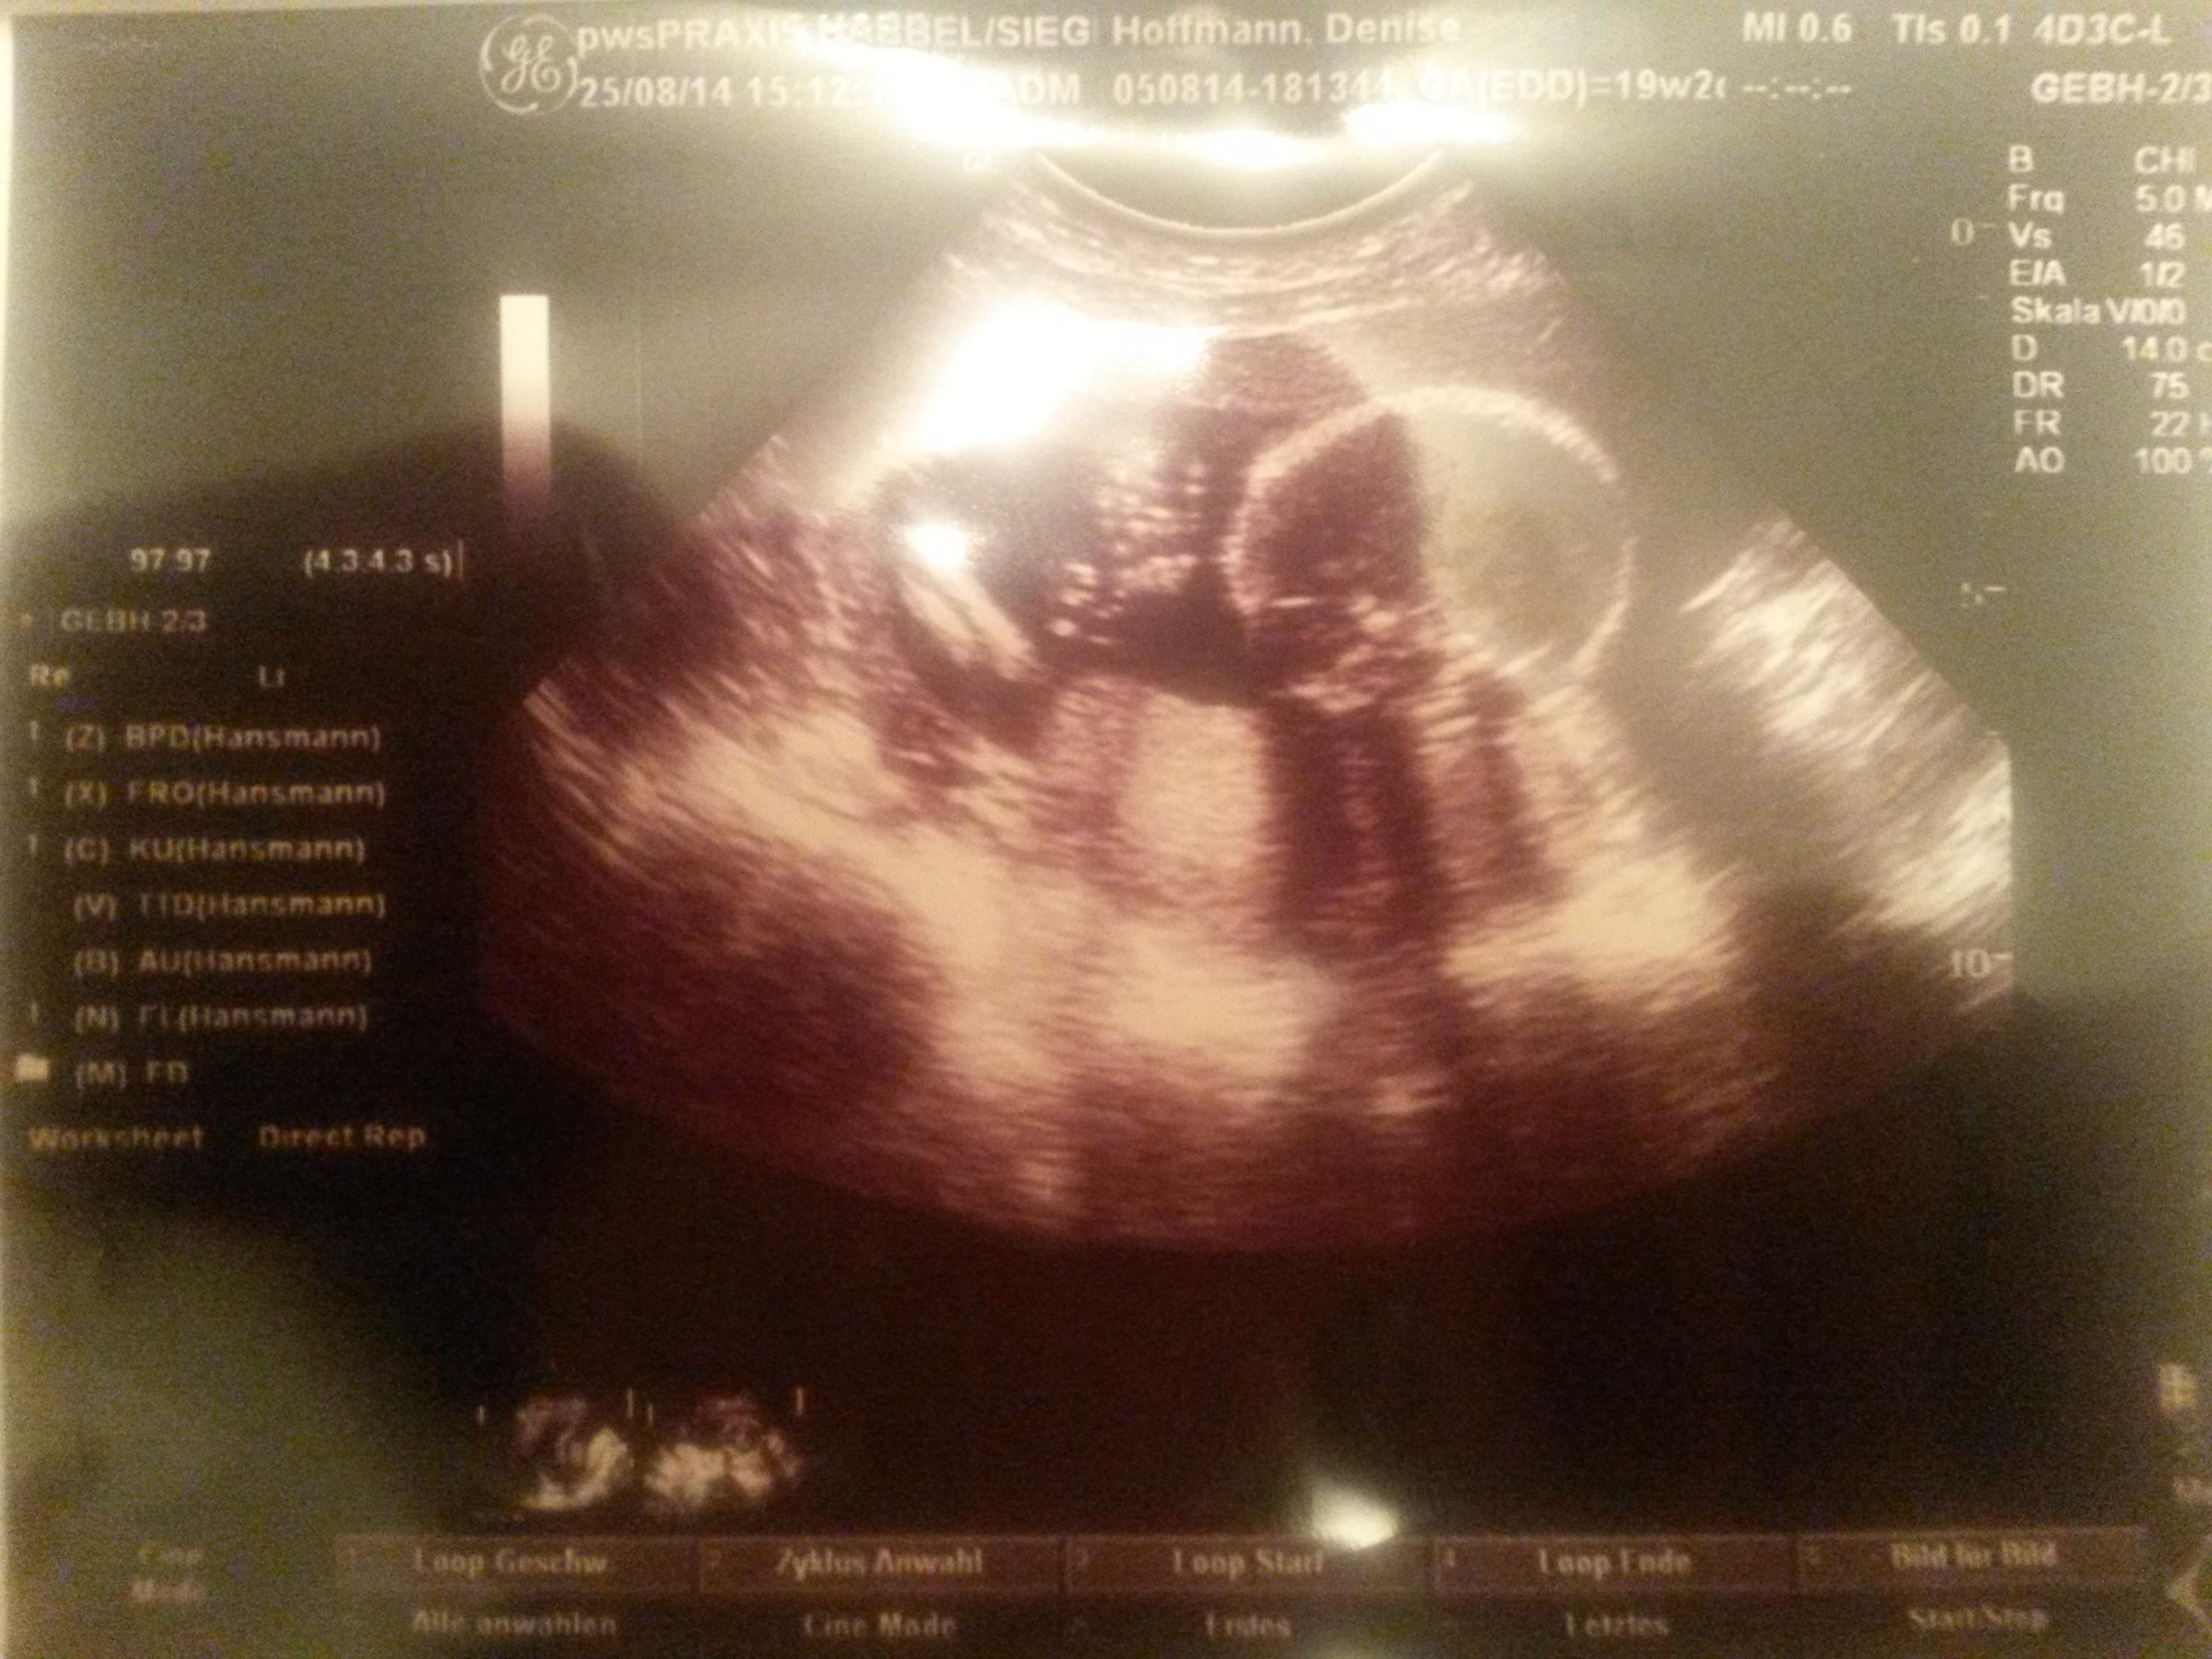

Auch wenn das Baby noch nicht da ist, macht es sich bemerkbar, winkt und feiert mit ;-)